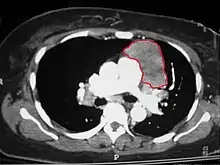

When a thymoma is suspected, a CT/CAT scan is generally performed to estimate the size and extent of the tumor, and the lesion is sampled with a CT-guided needle biopsy. Increased vascular enhancement on CT scans can be indicative of malignancy, as can be pleural deposits.[1] Limited biopsies are associated with a very small risk of pneumomediastinum or mediastinitis and an even-lower risk of damaging the heart or large blood vessels. Sometimes thymoma metastasize for instance to the abdomen.[5]

An encapsulated cystic thymoma.